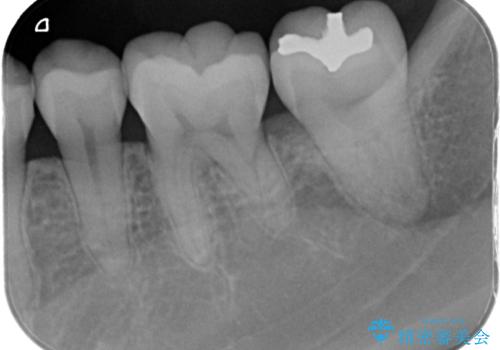

銀歯を白いセラミックに変えたい セラミックインレー

- 銀歯が気になるためやり替えたいとのことで来院されました。

セラミックインレーで治療を行いました。

口の中にチラつく銀歯は適合の良いセラミックインレーでやり替えることで綺麗にやり替えることができます。